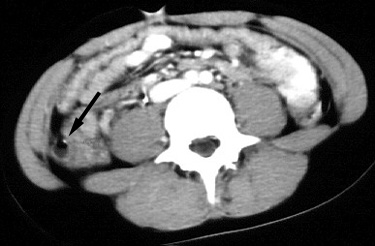

| Non-perforated appendicitis with multiple

appendicoliths, clinical symptoms mimicking psoas muscle

inflammation. 13 year old boy presented with three day history of right lower quadrant pain after weight-lifting which included squats. There was no history of nausea, vomiting, fever, or leukocytosis. On physical examination, positive peritoneal signs (abdominal guarding and rebound tenderness) were elicited. CT examination was performed to evaluate for possible abscess, shown below. |

Figure 1. Axial CT scan through the upper pelvis shows a fluid-filled, dilated appendix (arrowheads) which extends medially from the cecum (C), lying at the anterior aspect of the right psoas muscle (P on the right). The cephalad aspect of a calcified appendicolith is present in the appendiceal neck, shown more completely in the subsequent image (below). Multiple dilated, fluid-filled ileal loops (I) are present, which can result in diagnostic confusion unless the connection of the appendix with the cecum and a distal blind end can be identified. |